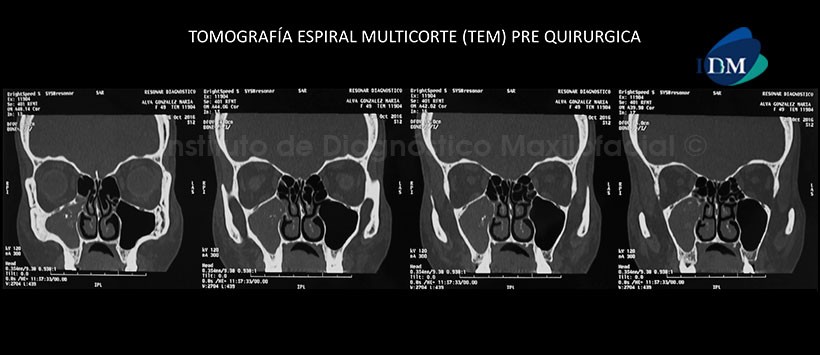

A la evaluación de la tomografía espiral multicorte (TEM) de diagnóstico, se evidenció la presencia moderada hipertrofia de cornetes inferiores, con concha bulosa bilateral. Así mismo se observa un contenido de densidad isodensa en la totalidad de seno maxilar derecho la cual a su vez presentaba calcificaciones internas. (Figura 1)